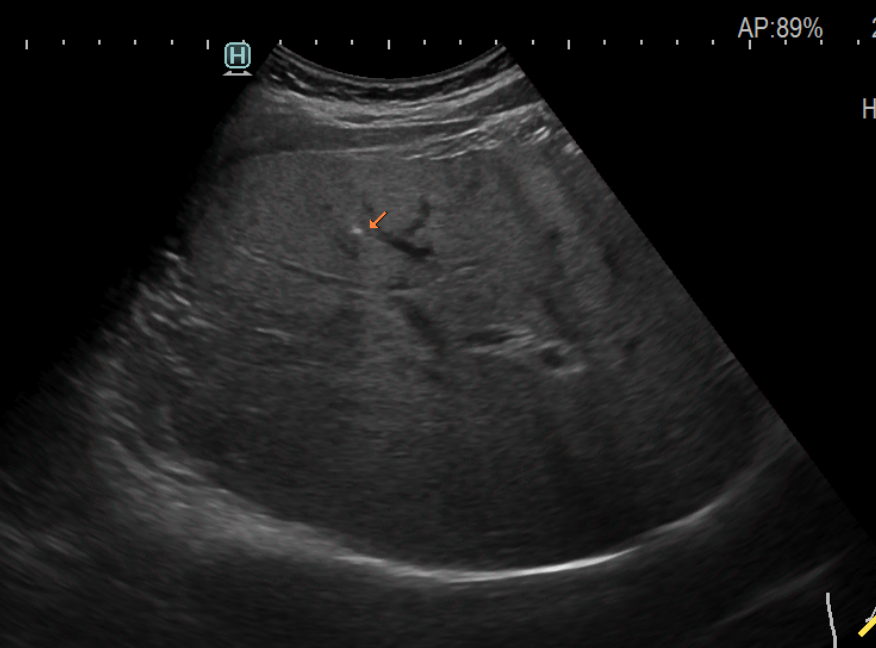

최근 건강에 대한 관심이 점점 많아지면서, 건강검진 때 여러 가지 검사를 해보는 경우가 많습니다. 그중 간을 보기 위한 영상 검사로 상복부 초음파가 많이 시행되고 있습니다.

상복부 초음파 검사에서 종종 나오는 결과 중 하나가 간 석회화라는 소견입니다. 석회화라는 단어가 들어가서 마치 내 간이 딱딱하게 굳었거나 막혀있다고 잘못 이해하고 걱정하는 분들이 종종 있어서 그에 대해 간략하게 알아보겠습니다.

사실 석회화는 우리 몸에 존재하는 대부분의 장기에 다 생길 수 있습니다. 이렇게 석회화가 생기면 주변 조직보다 단단하고 딱딱해지기 때문에 초음파나 CT와 같은 영상 검사에서 주변 조직보다 새하얗게 보이게 됩니다.